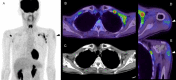

COVID-19 vaccination using mRNA technology began at the end of 2020 in several countries, approximately 9 months after the WHO declared the new coronavirus a pandemic, and began in Japan at the end of February 2021. Several studies have reported FDG avidity in enlarged axillary lymph nodes as a specific feature of FDG-PET/CT imaging after COVID-19 vaccination. A major concern is that this finding could lead to a misdiagnosis in patients with various types of malignancy. We review the impact of COVID-19 vaccination on the management of patients scheduled for FDG-PET/CT in the setting of nationwide mass vaccination.